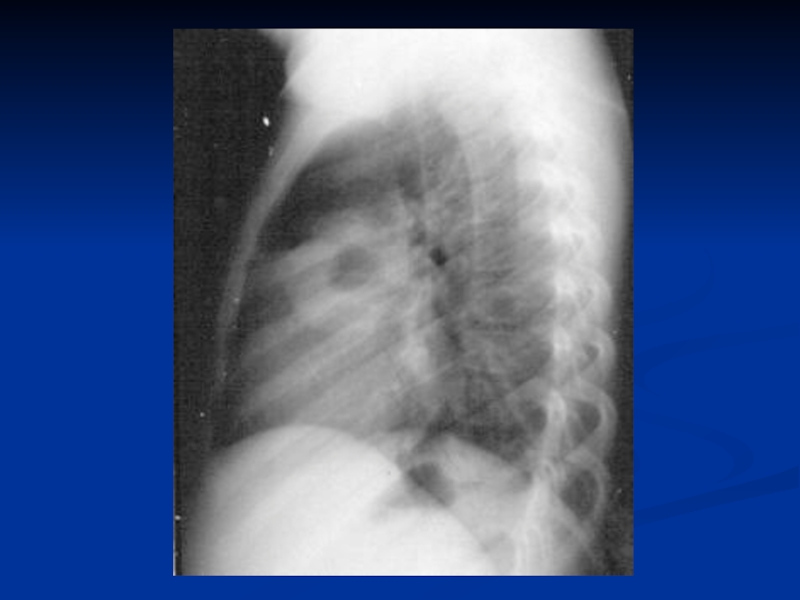

рентгенограмма: инфильтраты легочной ткани, чаще с обеих

сторон; усиление легочного рисунка в перифокальных участках.

повышение температуры тела; у незрелых новорождённых может быть нормальной;гемограмма: нейтрофильный лейкоцитоз, сдвиг формулы влево;рентгенограмма: инфильтраты легочной ткани,